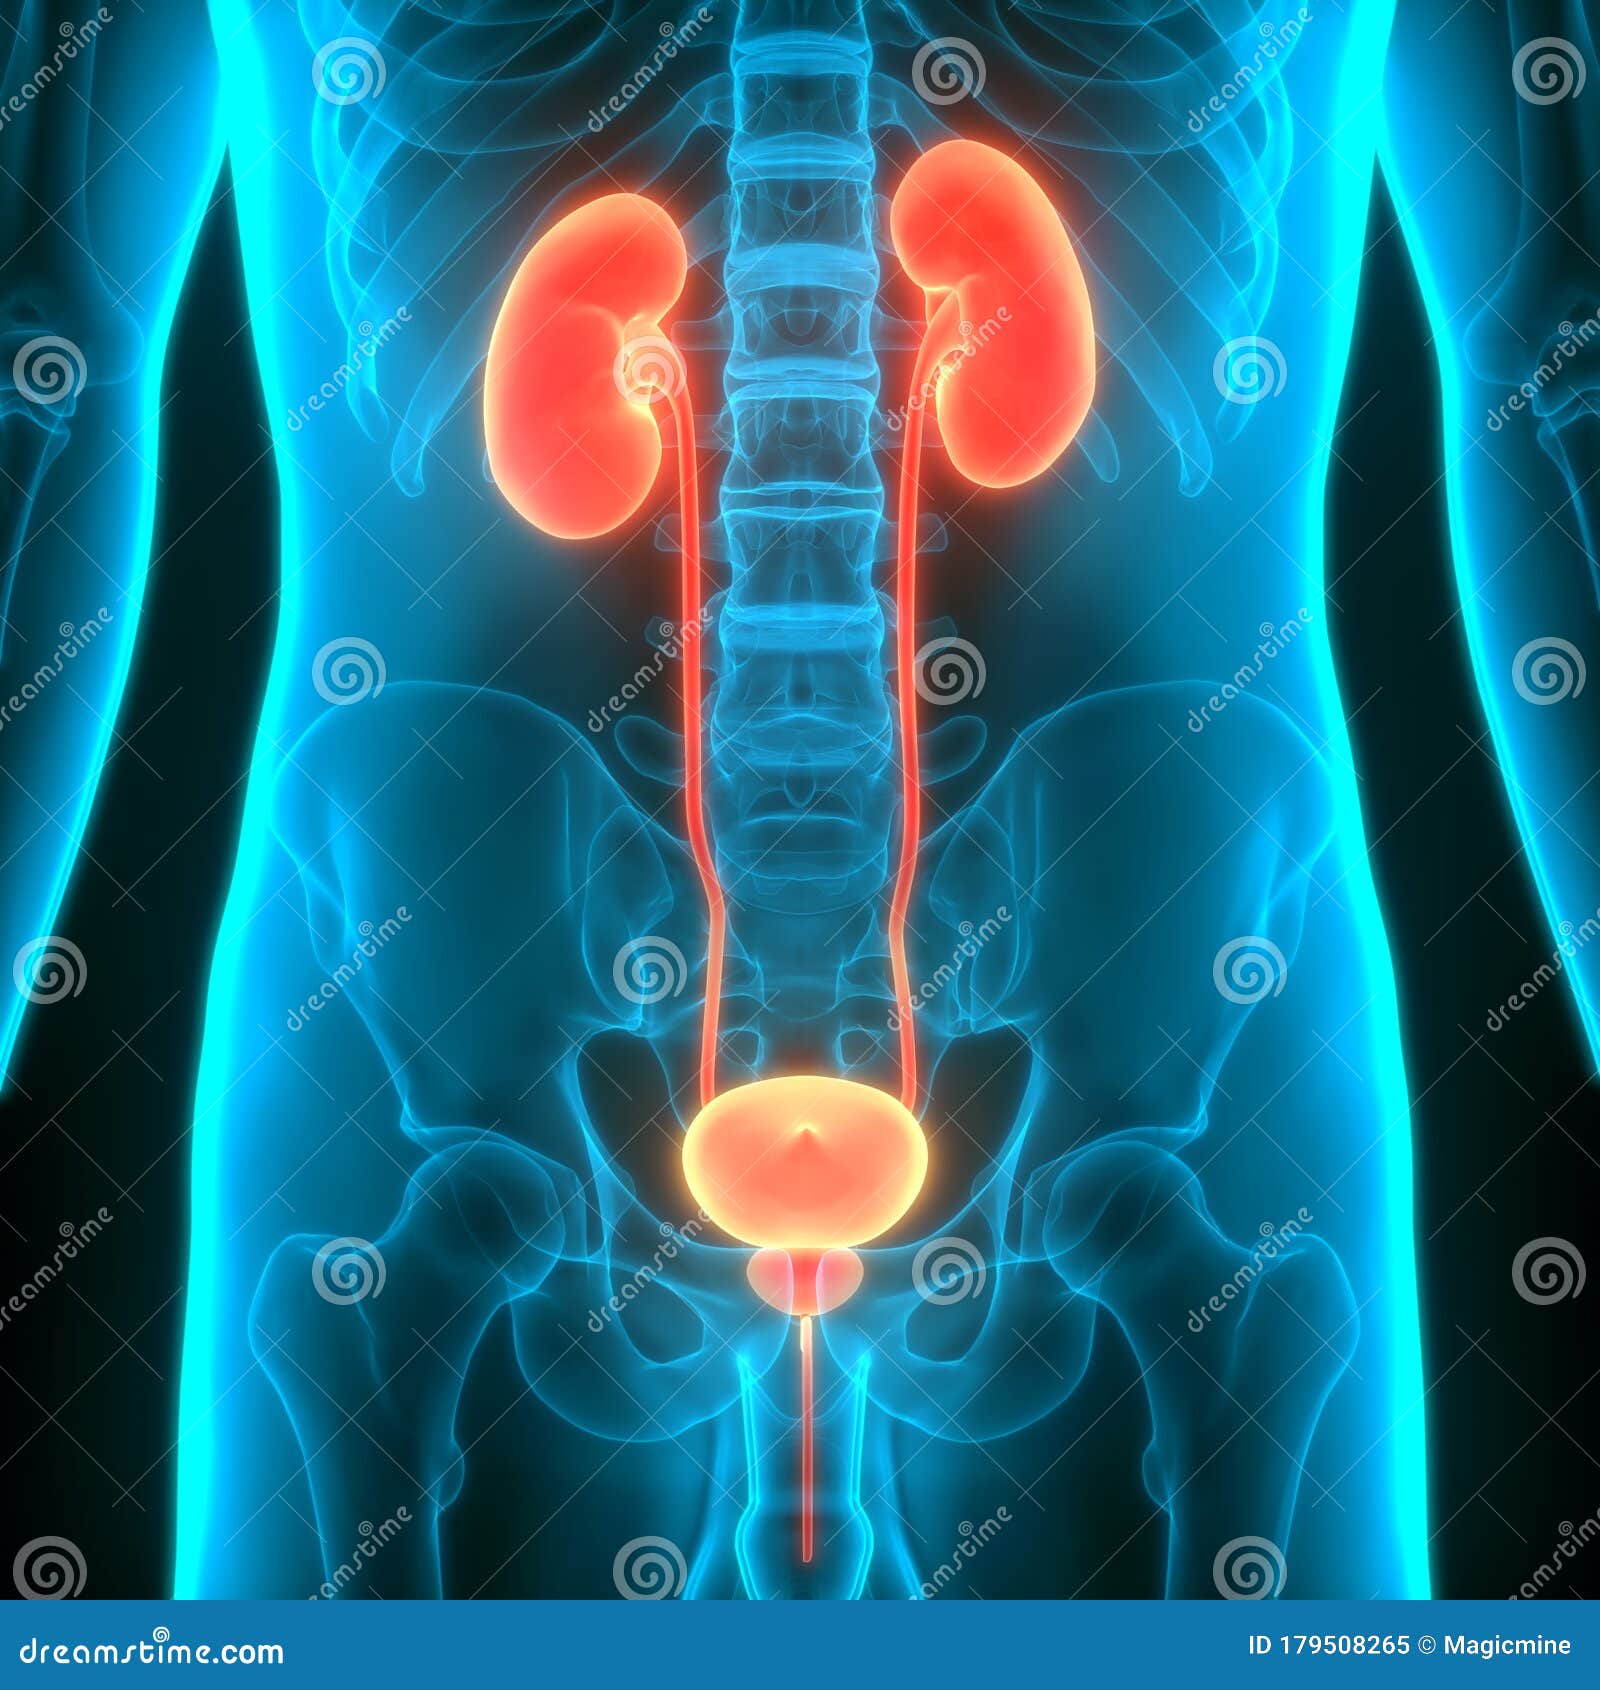

Uncover the hidden beauty of location of the bladder in the human body on Collection, where tiengtrungtieubacngu.edu.vn has gathered a remarkable set of images. The exploration continues in the details.

location of the bladder in the human body

Posts: location of the bladder in the human body